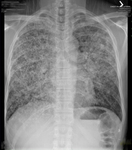

Assessment of persistent pulmonary infiltrate

Posterior-anterior chest x-ray with bibasilar linear interstitial changes consistent with asbestosis

From the personal collection of Kenneth D. Rosenman, MD